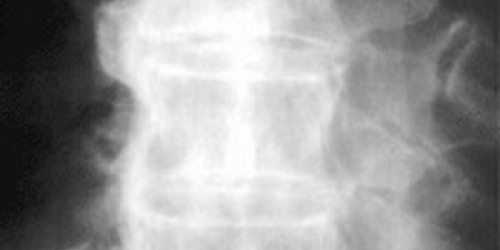

hello im a male aged 41, i have been suffering very painful shoulders, elbows and ankles for the last month.the pain is constant and i am very tired all of the time. my dr's have tested me for arthritus and it came back clear.they have also said i have diabetes. the trouble is i think the pain is getting worse. my neck is also have spells of stiffness. pls reply somebody. :'(